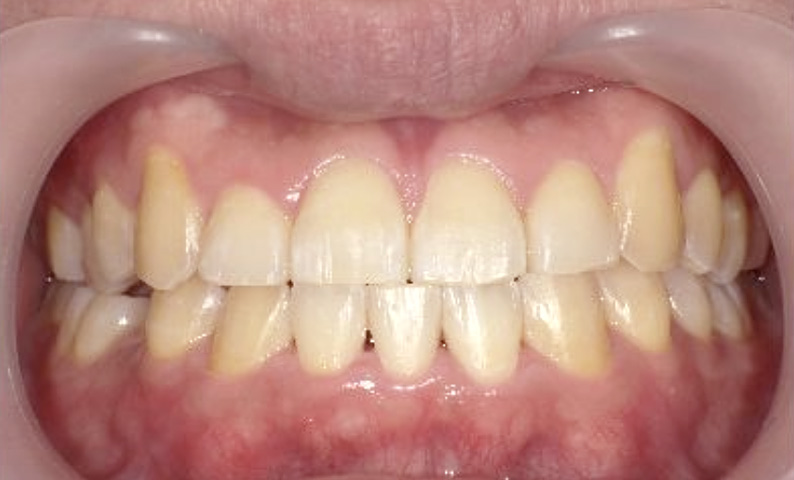

症例_001 下顎だけの部分矯正

治療期間:6ヶ月金額:27万円+税女性前歯のガタガタ下の前歯だけ

| Before | After |

|---|---|

|